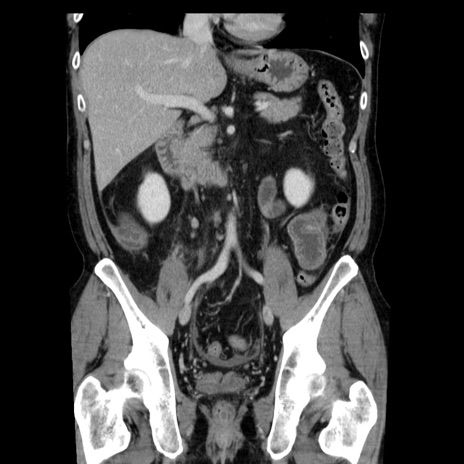

症例29(冠状断像)

【症例】40歳代男性

【現病歴】2日前から胃痛あり。徐々に周期的な激痛に変化した。本日になっても激痛があるため受診。

【身体所見】意識清明、BT 38-39℃台あり、腹部:膨満、やや硬、右下腹部に圧痛あり。

【データ】WBC 8500、CRP 23.26